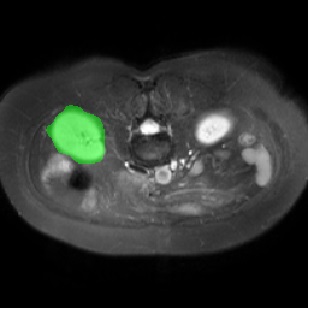

For CMR dataset, we only consider setting 1 because setting 2 is difficult to implement. The results are shown in Table 1 and Figure 4. In general, our proposed method is superior than others. For CHAOS dataset, we consider both setting 1 and setting 2. From the results, we can see the performance of our proposed model is higher than others on CHAOS and CMR datasets. Compared with Q-Net, our mean dice score on CHAOS dataset achieves about 82%. The segmentation results of the model are shown in Figure 5. In setting 2, the slices of the objects containing the test classes are all removed at training stage, and our model still performs well. As can be seen from the Table 2, the segmentation effect of the model on the right kidney is slightly worse than that of ALPNet, but overall, we achieve the best performance. The specific segmentation results are shown in Figure 6. As can be seen from the figure, other methods have excessive segmentation, but ours does not. Our segmentation results are more accurate and reduce redundant segmentation.